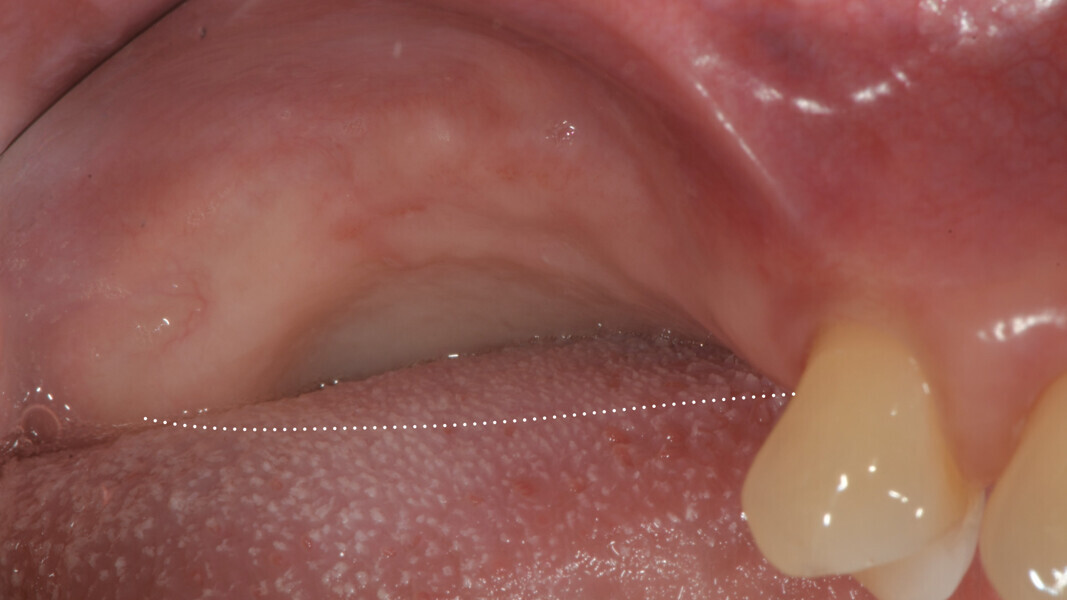

A 62-year-old female patient (ASA Class I), a non-smoker and with normal glucose levels, with previously treated periodontal disease presented for implant and prosthetic rehabilitation of the upper jaw (Fig. 1). Radiographic analysis, performed through a dental panoramic tomogram and CBCT scan, revealed the presence of a vertical bone defect in the right posterior sextant, due to the complete loss of the alveolar process (Figs. 2; 3a & b). The clinical examination showed the severity of the bone defect, which had resulted in an obvious volume deficiency in both the horizontal and vertical dimensions (Figs. 4 & 5).

The surgery began with a semilunar incision into the alveolar mucosa on the buccal side of the area to be treated, associated with two vertical vestibular incisions (Figs. 9 & 10).19 A full-thickness flap was then elevated on the buccal side and subsequently mobilised with a periosteal incision, followed by a superficial dissection to separate the mucosal layer from the underlying muscle (Figs. 11 & 12). A full-thickness flap was also elevated on the palatal side, isolating the greater palatine artery (Fig. 13).